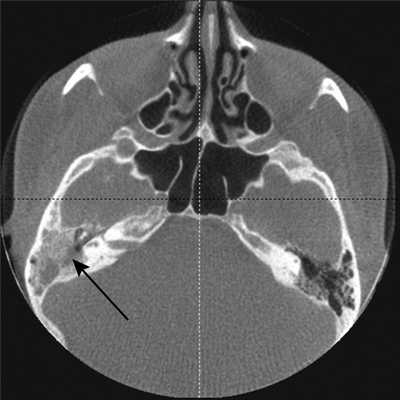

Характерным КЛКТ-признаком, обнаруженным у всех больных, являлось нарушение пневматизации полостей среднего уха за счет наличия в них патологического субстрата, являющегося отображением утолщенной слизистой оболочки, грануляций и гноя. Данный признак проявлялся на томограммах повышением плотности в воздухоносных полостях до значений, характерных для жидкости и мягкотканных структур. Частота поражения была различной. Нарушение пневматизации адитуса, антрума и ячеек сосцевидного отростка было выявлено в 33 (69%) из 48 височных костей. В зависимости от степени выраженности изменений выделялось частичное и тотальное нарушение пневматизации. При частичном отсутствии пневматизации, выявленном в 8 (16%) височных костях, определялся как воздух, так и патологический субстрат с вогнутыми контурами. При тотальном нарушении пневматизации в 4 (8%) наблюдениях патологический субстрат полностью вытеснял воздух (рис. 1, а). Рисунок 1. Конусно-лучевая компьютерная томограмма височных костей в аксиальной плоскости. а — барабанная полость полностью заполнена мягкотканным и жидкостным содержимым (указано стрелкой)ыши барабанной полости (указан стрелкой).

Деструктивный процесс в стенках барабанной полости и антромастоидальной области встречался нечасто у больных хроническим гнойным средним отитом - в 6 (12%) височных костях из 48 (рис. 1, б). Рисунок 2. Конусно-лучевая компьютерная томограмма височных костей в аксиальной плоскости. б — участок деструкции крыши барабанной полости (указан стрелкой).